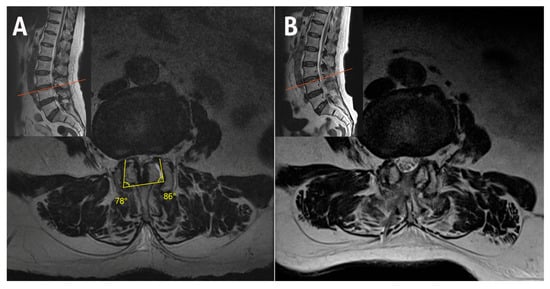

2.3. Case 3: Bilateral–Contralateral Decompression in Spondylolisthesis